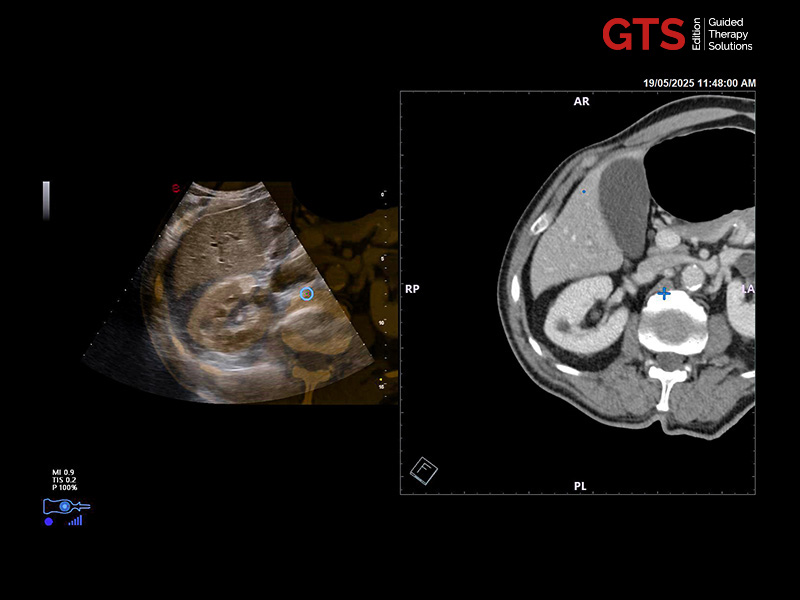

Expert users and beginners can now achieve a heightened degree of simplicity and precision by using UroFusion, Esaote’s cutting-edge fusion imaging solution that makes the most of the combination of US and MR or PET modalities.

By harnessing Augmented Insight™ (A.I.) technology, our dedicated solution enhances workflow efficiency by Automating MR Prostate Contouring & Segmentation with instant and automatic US-MR Synchronization, applied to both transperineal (TPUS) and transrectal (TRUS) prostate biopsy approaches.

Using UroFusion, clinicians will benefit from our intuitive tools to fasten the fusion procedures: the automatic prostate contouring and biopsy sample mapping are certainly the most impressive.

UroFusion seamlessly offers the ability to combine different mpMRI series, facilitating the identification of suspicious prostate lesions.

mpMRI targeting phase of PI-RADS 5 peripheral lesion